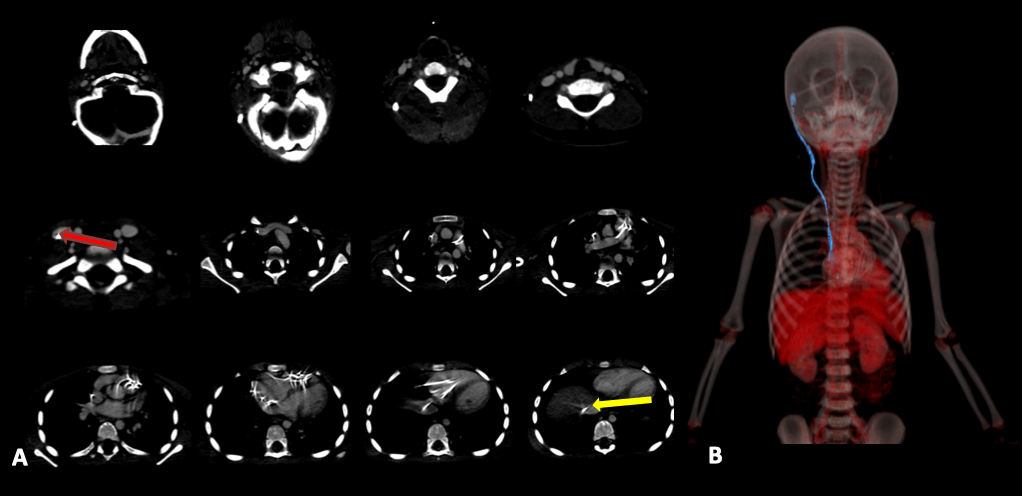

Paciente de 3 años, con antecedente de tumor de fosa posterior (TFP) e hidrocefalia, que debutó con síntomas de hipertensión endocraneana y ataxia de 3 semanas de evolución. Consultó a otra Institución, donde se colocó una DVP y se derivó a nuestro Hospital. Se realizó de forma programada resección del TFP sin complicaciones y con buena evolución. A los 5 meses de la colocación de la válvula, consultó por cefalea, náuseas y vómitos. Se estudió con Tomografía cerebral, que evidenció dilatación ventricular, y radiografías del sistema (Figura 4) que mostraron la ubicación intracardiaca del catéter distal. Se completaron los estudios con una tomografía de tórax (Figura 5) que informó la posición anómala del catéter distal, que se introducía en las cavidades cardiacas derechas, posteriormente en la arteria pulmonar, volviendo a las cavidades derechas e introduciéndose en la vena cava inferior con localización de la punta del catéter a nivel de la vena suprahepática derecha. No se observaron trombos relacionados con el catéter. Junto a los Servicios de Intervencionismo y Cirugía Cardiovascular se realizó la revisión valvular bajo monitoreo cardiológico continuo y radioscopia. A través de una incisión paralela a la válvula se retiró el catéter distal y se lo recolocó a la cavidad peritoneal. El paciente evolucionó favorablemente y fue dado de alta.

Figura 5: A) Tomografía computarizada de tórax del Caso 2. Se señala la posición anormal del catéter distal, que ingresa en las cavidades derechas a través de la vena yugular interna (flecha roja), alcanzando posteriormente la arteria pulmonar, para después volver a las dextro cavidades e introducirse en la vena cava inferior con localización de su extremo distal a nivel de la vena suprahepática derecha (flecha amarilla). B) Reconstrucción 3D del catéter distal ingresando al atrio derecho.